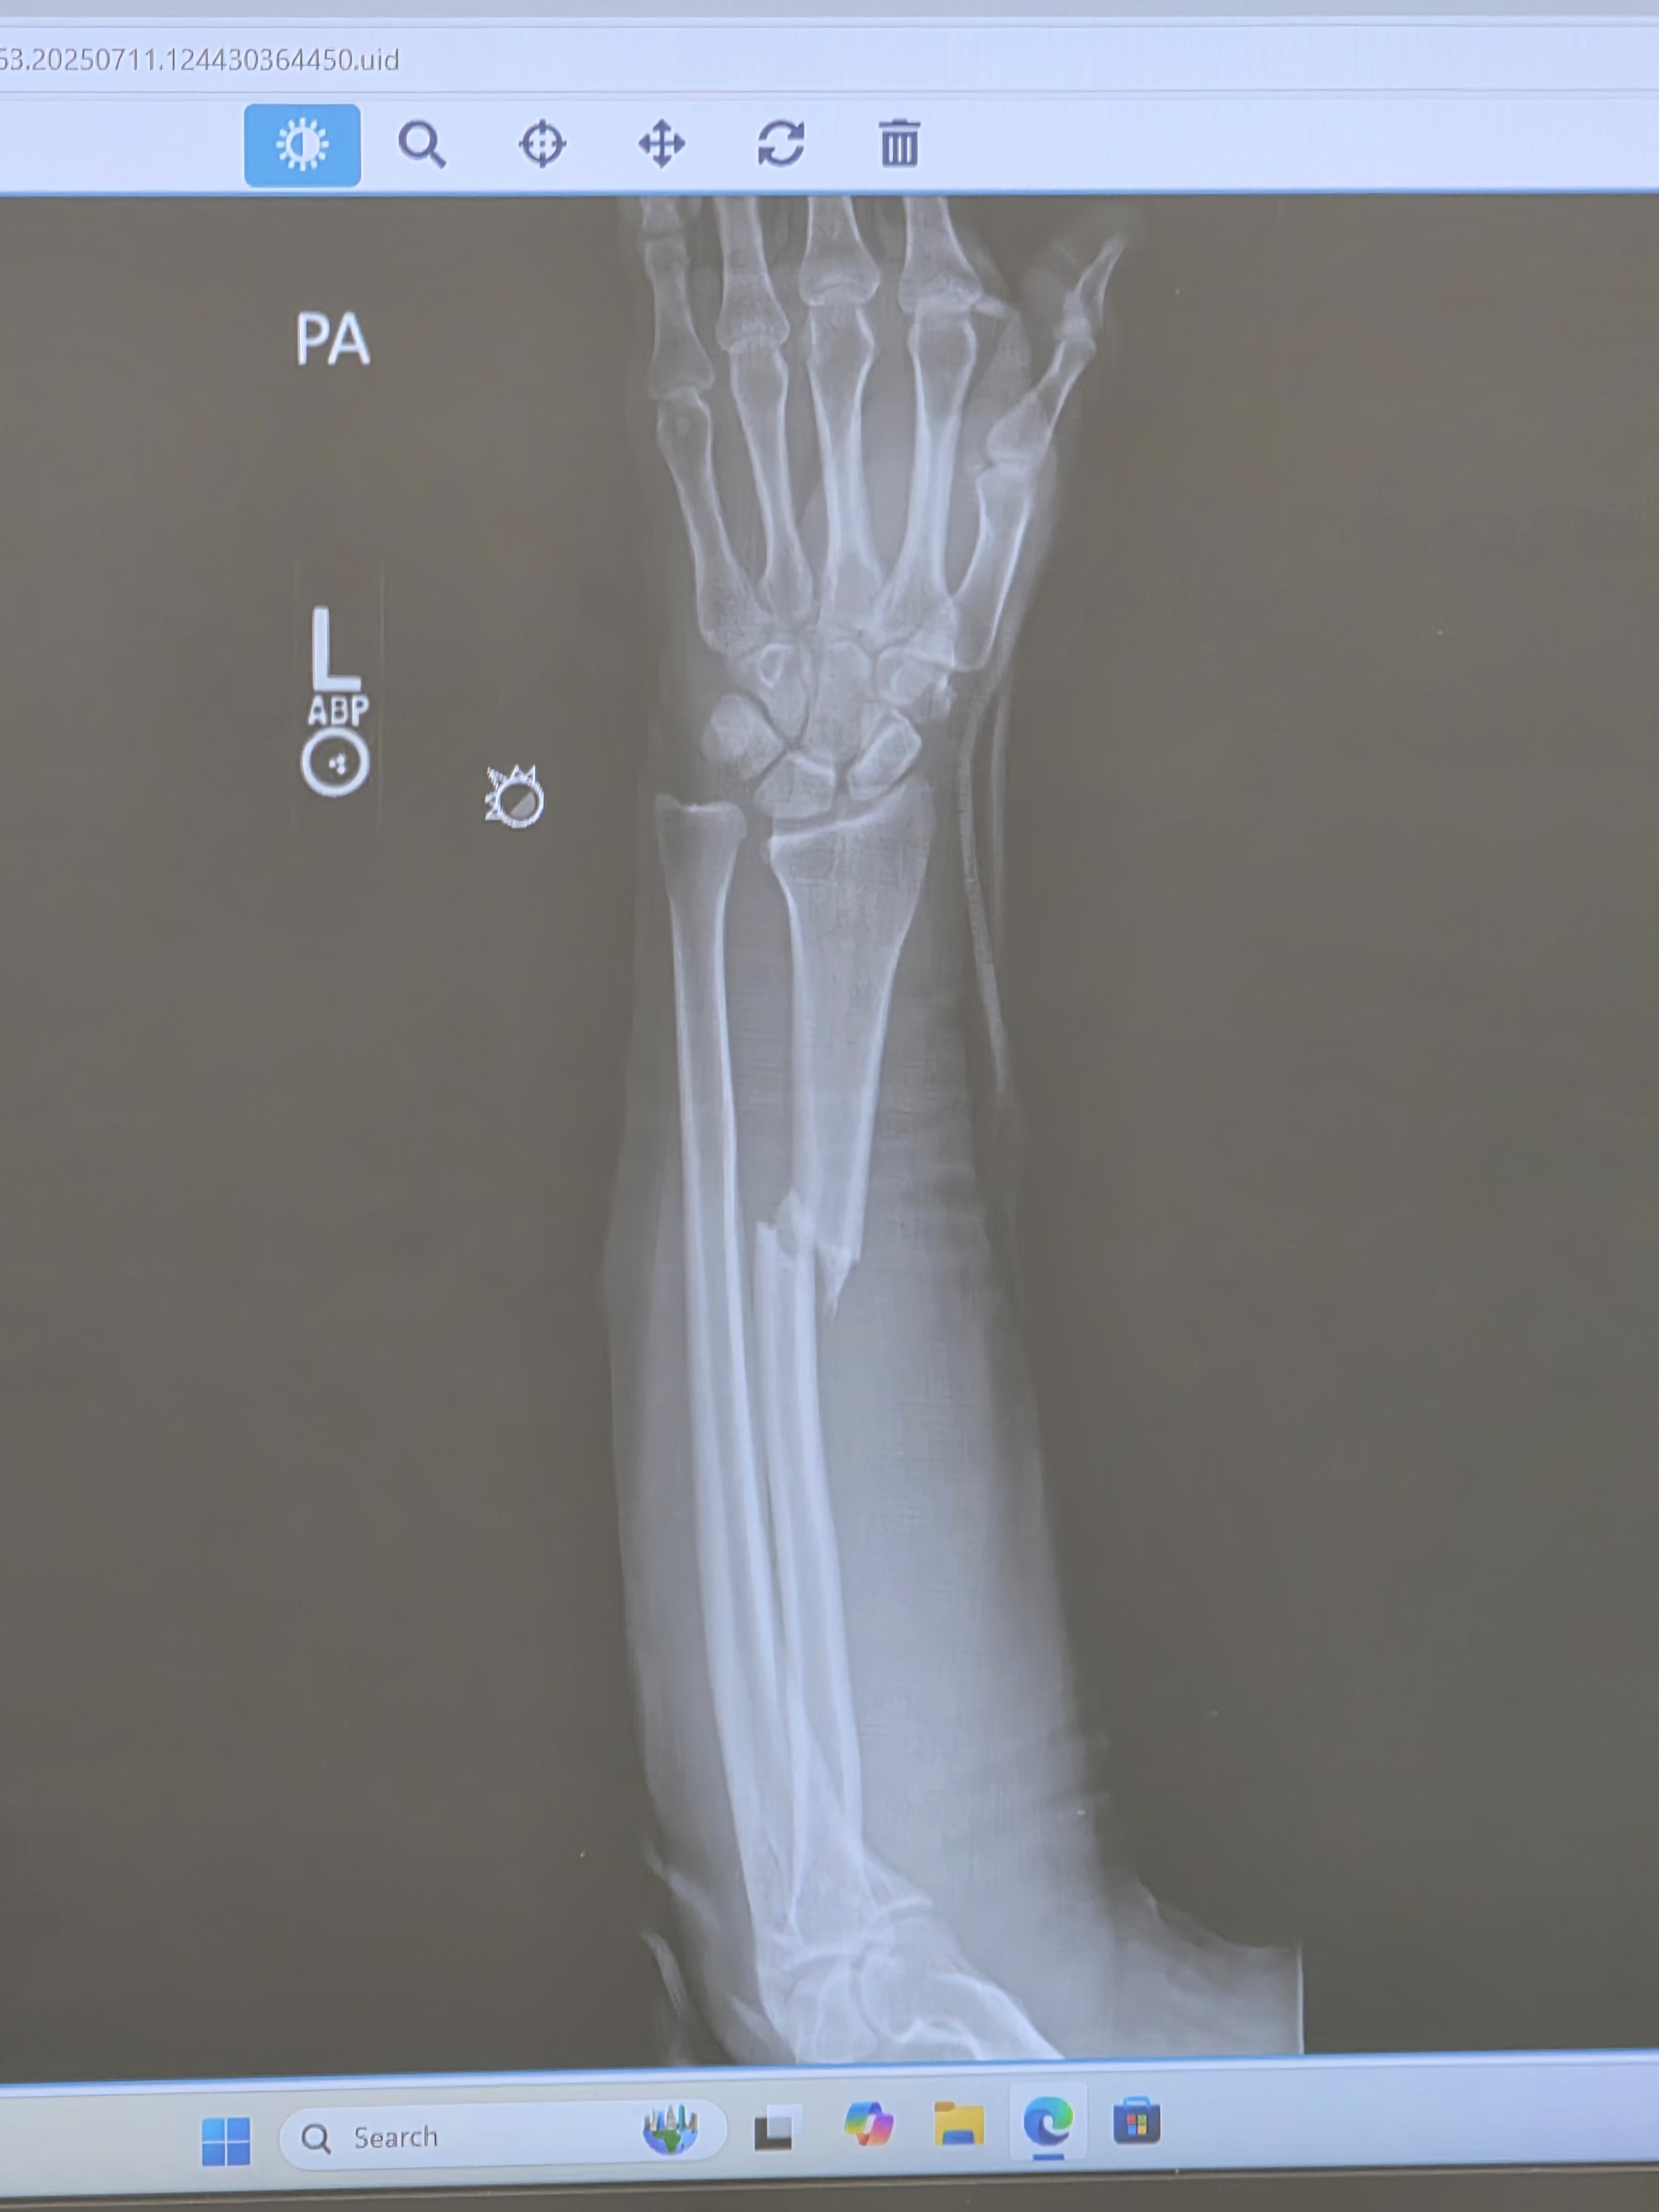

Hello, my name is DJ. I recently had an accident which broke my left radius in half, it requires a plate and screws. I'm going in for surgery Tuesday the 15th, and apparently, my insurance is not covering my surgery. It's over 12,500 dollars, This is a huge hit, not to mention not being able to work. I'm a self-employed business owner, and I subcontract as well, and have not been able to do any of that work due to the injury. I've never been one to look for handouts; I've always worked my ass off for everything I've gotten, so it kills me to have to ask anybody to contribute anything to help right now, but my family and I can really use any assistance. The bills are piling up, and I literally can't do anything about it at the moment! I've never felt this helpless in my life! I'm used to giving it 110% all day long until I quit, and now my body is in pain! I'm trying to heal as fast as possible so that I can get back to work and take care of business again!